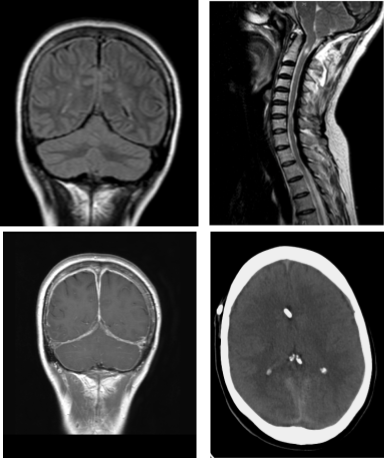

La resonancia magnética (RM) de cráneo y columna cervical mostró ventrículos de muy pequeño tamaño y un engrosamiento de la duramadre craneal que afectaba a la hoz cerebral y al tentorio, así como un engrosamiento del ligamento amarillo mayor a nivel C7-D1 (Figura 1). La fosa posterior, de pequeño tamaño, mostraba una adecuada descompresión, con imagen de hiperintensidad central a nivel de C2 como secuela de una siringomielia ya parcialmente resuelta. El engrosamiento dural era lineal y realzaba con gadolinio, dejando un centro hipocaptante, especialmente a nivel de la hoz. El ligamento amarillo engrosado no captaba contraste.

Figura 1. RM cráneo y columna cervical. Arriba a la izquierda, imagen en T2 donde se ve el tentorio y la hoz hipointenso y engrosado. A la derecha, RM de columna cervical sagital que muestra el engrosamiento del ligamento amarillo a nivel cérvicodorsal y los restos de siringomielia cervical tras la descompresión de fosa posterior. Abajo, izquierda, cortes coronales en T1 con gadolinio, observándose la captación de la duramadre de la convexidad, del tentorio y de la hoz, con una zona hipointensa en el interior, sobre todo en la hoz cerebral. A la derecha, TC de cráneo con catéter proximal normoposicionado y ventrículos en hendidura.